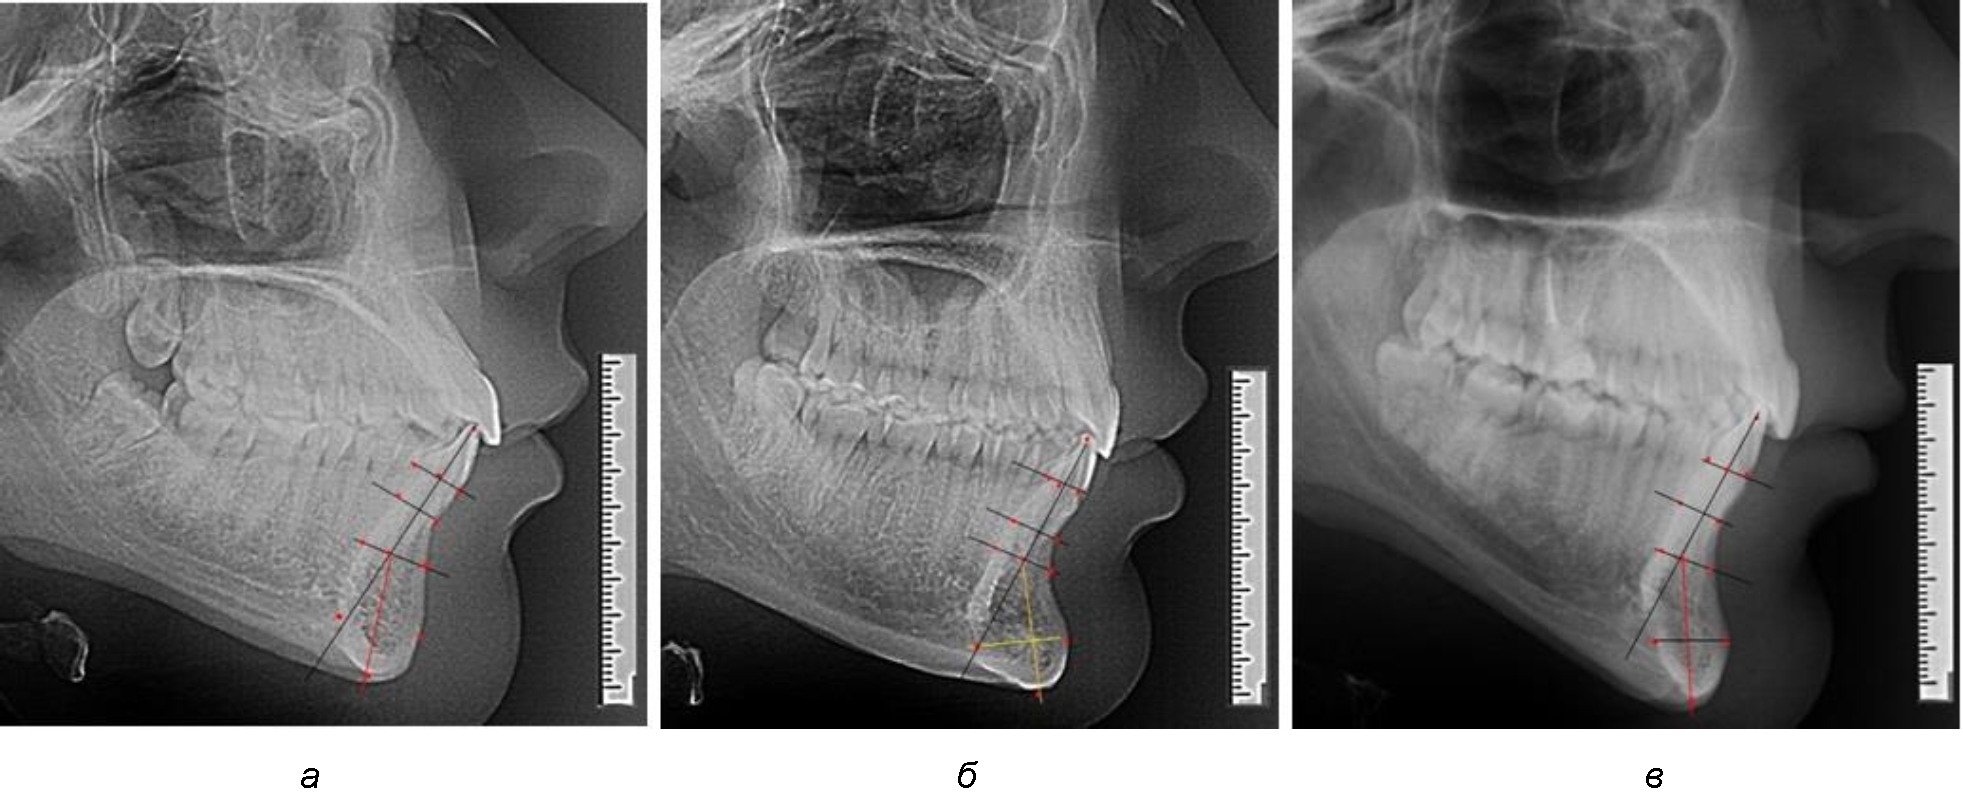

На режущем крае нижнечелюстного резцового сегмента устанавливалась точка, обозначаемая как IsL.

Определяли положение цервикальных точек резцов на вестибулярной и лингвальной поверхностях, которые соединяли цервикальной линией. Условная срединную вертикаль зуба соединяла резцовую точку IsL с серединой цервикальной линии и, как правило, доходила до апикальной точки, которую обозначали как Ap. Линия IsL–Ap определяла высоту зубоальвеолярной части резцового нижнечелюстного сегмента. Определяли высоту коронки и корня зуба. Кроме того, на вестибулярной поверхности зубочелюстного сегмента отмечали точку наибольшей вогнутости альвеолярной части, которая обозначалась как супраментальная точка Downs (Bsm). Измерялось расстояние IsL–Bsm, которое служило для определения проекции супраментальной точки Downs на язычную поверхность сегмента и обозначалась как точка Bsm'.

Проекцию верхушки корня резца на кость обозначалась как точка B нижнего апикального базиса по Schwarz. Соединяли апикальную точку с точкой нижнечелюстного апикального базиса линией, которая доходила до язычной поверхности подбородочного выступа и определяла положение точки B'. Таким образом, в зубоальвеолярной части сегмента выделялись две зоны: верхняя и нижняя, с последующим измерением по вертикали. При этом, как правило, верхняя зона была представлена компактной костной тканью, а в нижней зоне определялось наличие губчатой ткани между компактной пластинкой и стенкой альвеолы.

На нижнем контуре подбородочного выступа определяли положение ментальной точки Me. Линия, соединяющая апикальную точку с ментальной, определяла высоту подбородочного выступа тела нижней челюсти. Высота зубочелюстного сегмента IsL–Ме измерялась от резцовой до подбородочной точки. Вертикальная линия Ap–Me делила подбородочный выступ на две части: переднюю и заднюю (рис. 1).

Рис. 1. Ориентиры для исследования нативных препаратов (а) и рентгенограмм (б) резцового нижнечелюстного сегмента

Сагиттальные размеры зубоальвеолярной части сегмента определялись между точками Bsm и Bsm', в апикальной части сегмента – B и B'. В подбородочной части сегмента из передней выступающей точки подбородка Pog проводили линию перпендикулярно к линии Ар–Ме с определением точки Pog'. Расстояние Pog–Pog' определяло ширину подбородочного выступа.